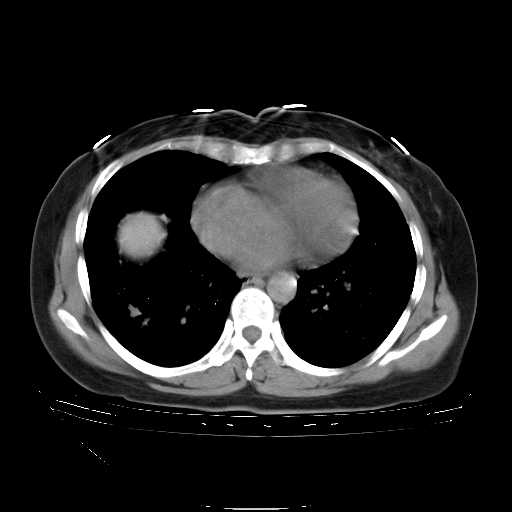

下面是今天刚刚做的,在上海治疗,吃了家属也说不清的一种药,一个月1万左右,

考虑  腺癌肺内转移,治疗较前病灶缩小、减少

肺癌并肺内转移,这种疾病治疗后在影像上看略有好转,不是很显著,但是肿瘤治疗效果影像只是一方面。

支持肺癌并肺内淋巴管炎,  原发灶小了,但转移较前片明显了.

支持右肺下叶周围型肺癌并肺内淋巴管炎,  原发灶小了,但转移较前片明显了.。